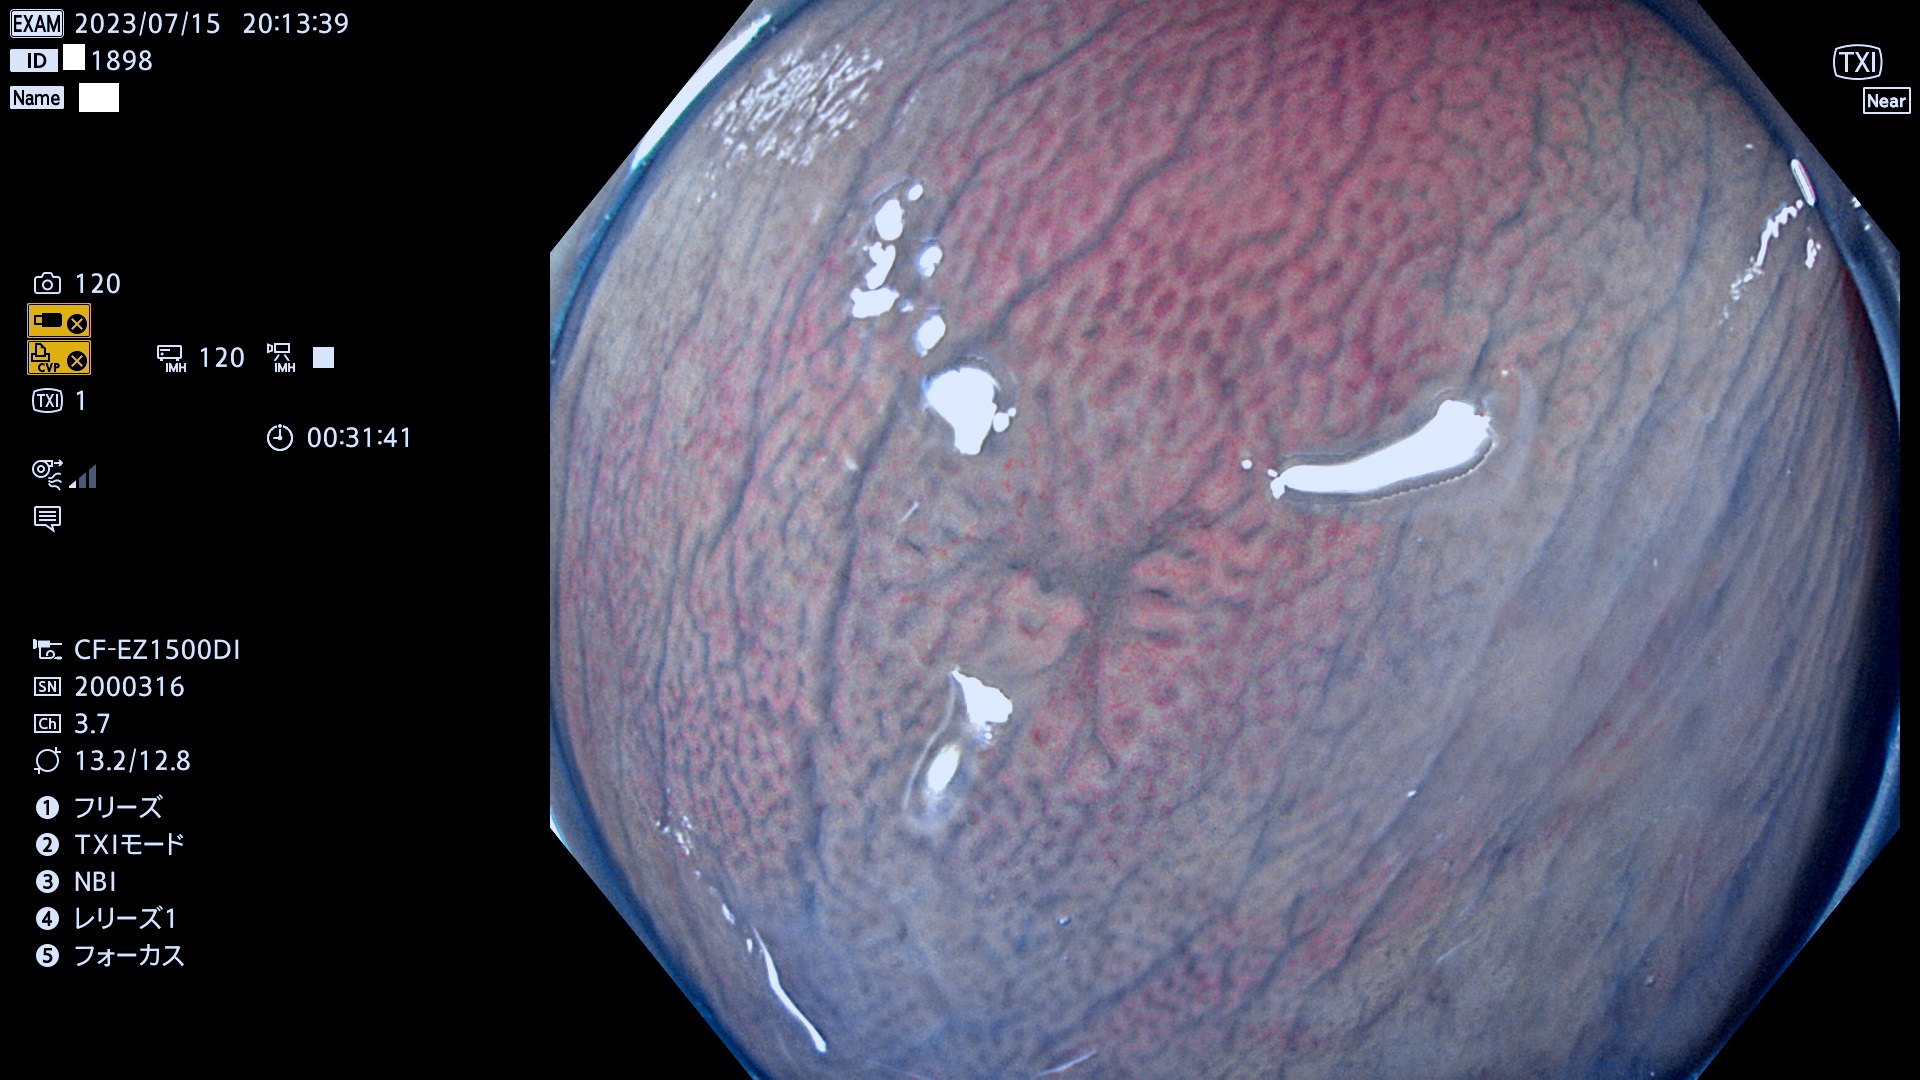

大腸Ub、Uc型・腺腫とは?

「表面型腺腫(Flat Adenoma)の中で、完全に平坦な物をUb、陥凹している物をUcと呼びます。平坦隆起型(Ua)よりも、発見が難しく危険な病変です。このタイプの発見率は「腺腫発見率」よりも、遥かに重要な意義があります。

毎週の検査(木・金・土・日)に発見されたUb、Uc型・腺腫を、その週の日曜の夜にUPし1週間、提示します。

抽出の対象期間 2023年7月13日(木)〜7月16(日)の4日間(48件の検査)8件